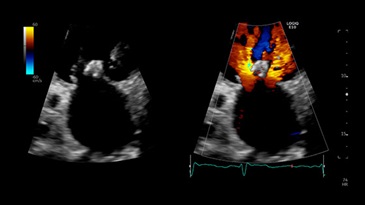

Поток регургитации на двойном экране с ЦДК, M5Sc-D